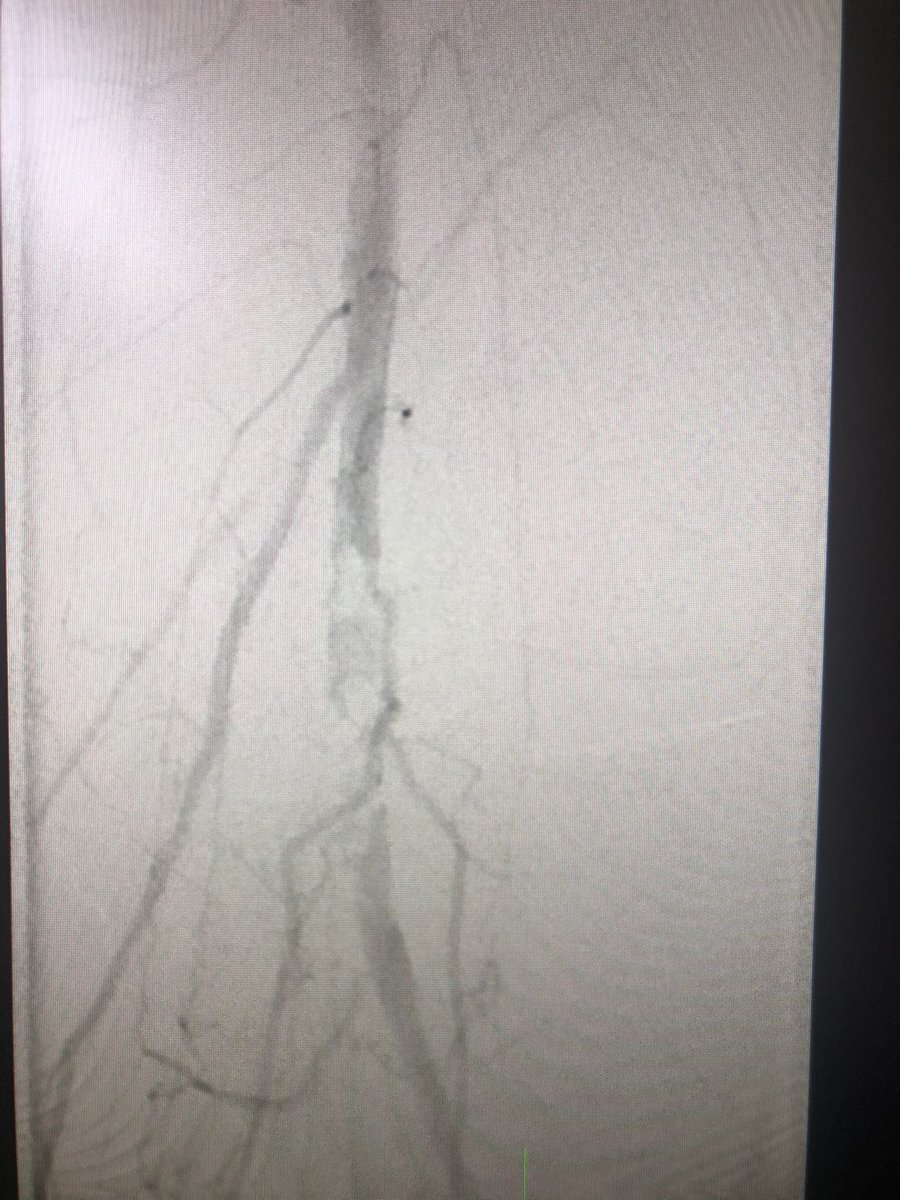

Step 5 - tackle the task at hand! In this case a complicated restenosis of a mixed plaque of popliteal artery. Having had good access - you have piece of mind in proceeding with high quality intervention. #PeripheralIntervention #JointCathConference

Step 6 - post intervention moment of #mindfulness - take a moment to appreciate the yrs of training &skill development that it takes to make a profound change in someone’s life. No two procedures are the same. No two people are the same. Learn from each case! #JointCathConference